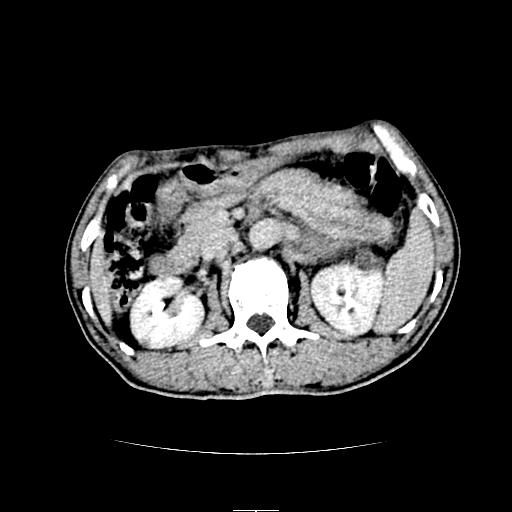

考虑胰腺巨大囊肿,左肾低密度灶从形态和强化方式看不象囊肿,应考虑肿瘤。

左上腹胃、脾及胰腺间巨大囊性占位性病变,其内见多数薄隔,有轻度强化,明显占位效应。左肾见一小囊性变。

左肾囊肿;网膜巨大囊肿。